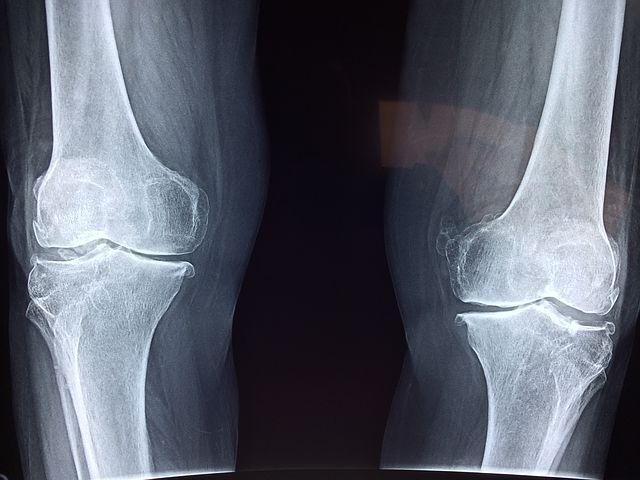

시간이 지나면서 관절이 파괴되기 시작하면 작은 관절도 생활에 큰 불편함을 초래하기 시작합니다. 더 나아가 큰 관절로 번지게 되기도 하며 면역 체계 이상에 따른 심각한 합병증 등으로 악화 되기도 합니다.

손, 발가락 같은 작은 관절에 발병하는 경우가 대부분이지만, 기간이 길어지고 치료가 늦어짐에 따라 무릎, 어깨, 허리 등 큰 관절에 염증이 전이되는 경우가 발생합니다. 완벽한 요인이 밝혀지지는 않았으나 유전, 흡연 습관, 잇몸 질환 등과 관련이 있다고 보고되고 있습니다.

변형이 심하여 일상생활에 방해가 되거나 증상이 심해 관절의 파괴를 피할 수 없는 중증 환자에게 시행됩니다. 상태에 따라 인공 관절 성형술이나 고정술 등을 고려합니다.